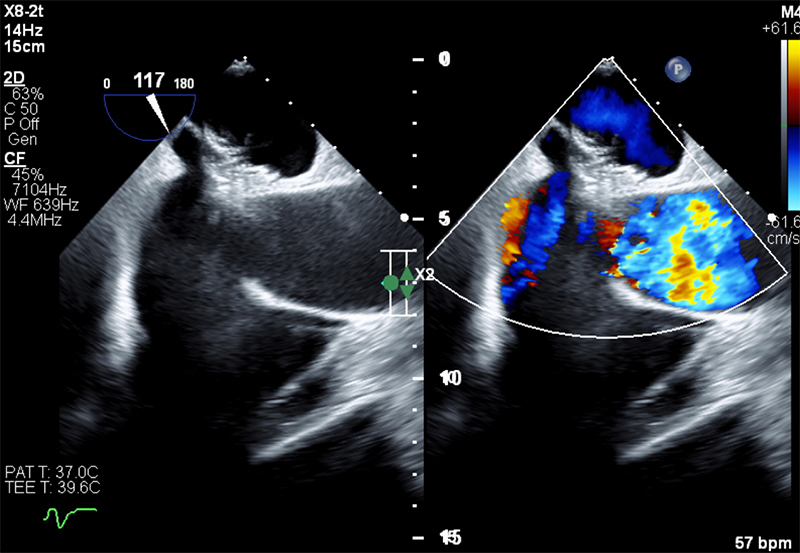

The patient was transferred to the tertiary cardiac centre for PFO closure (figure 3), which was completed with no complications using a Gore septal occluder device. Follow-up confirmed complete symptom resolution including positional hypoxia.